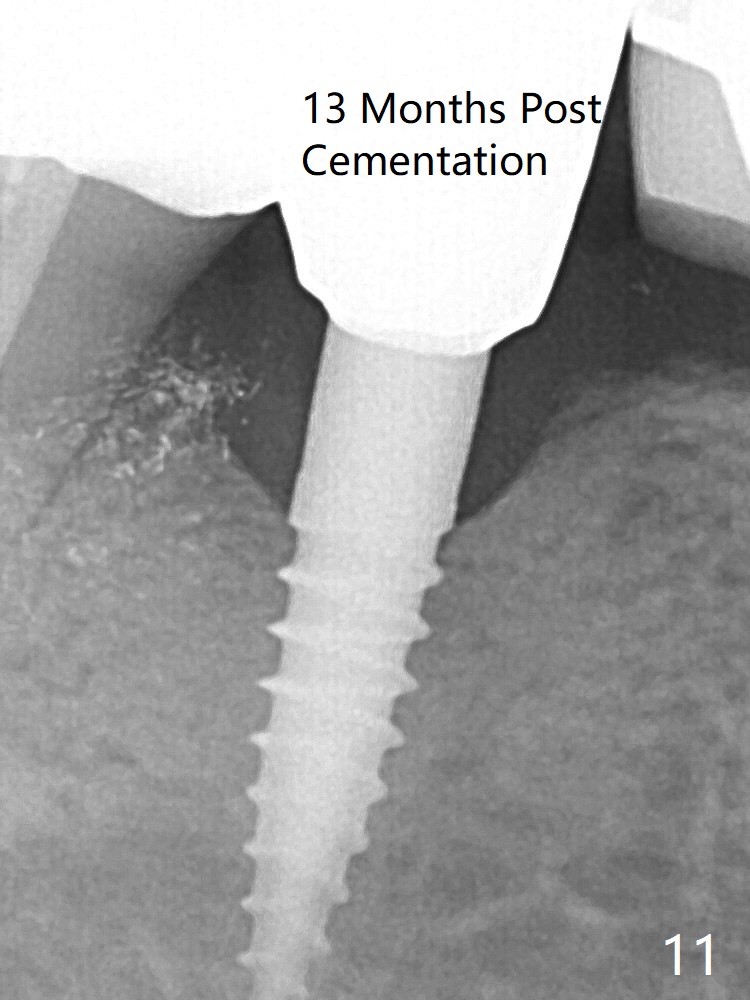

In fact the crown at #30 is redone because of loose proximal contact with #31; there is no bone resorption 13 months post cementation (Fig.11). The crestal bone loss is observed 3 months postop (Fig.6 arrowheads), as related to ridge reduction (cortical bone). Since then, there has been no bone resorption.